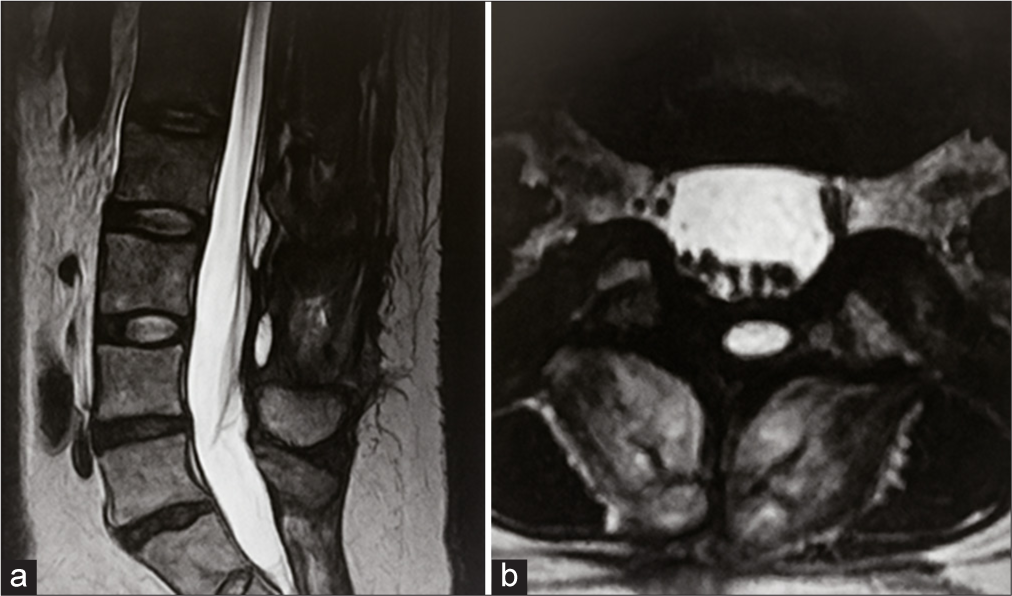

A ressonância magnética de controlo confirmou a remoção completa da lesão, sem evidência de tumor residual, validando o sucesso da intervenção cirúrgica.

Imagem 4: Ressonância magnética pós operatória confirmando remoção completa do tumor.